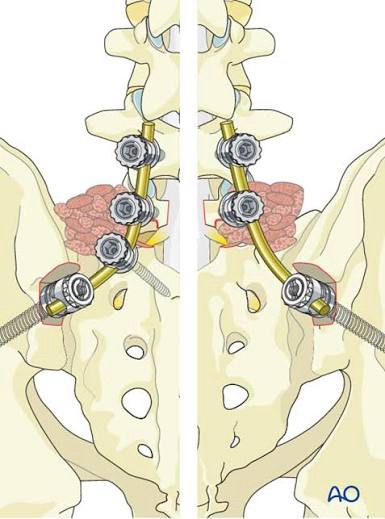

At my 3-month post-op appointment, my surgeon lifted all my restrictions and said I can return to all activity, “just listen to [my] body.” She measured my X-rays (above) and said my lumbar curve decreased 20 degrees, and the thoracic is the same. Also, I grew half an inch. I showed her the scoliosis program I found in New Hampshire, and she was all for it. I’ve booked a furnished apartment in New Hampshire 4/20-5/31 and scheduled the 12 sessions of treatment at the PT clinic there. I’m hopeful that will help with my back pain, and maybe even reduce my thoracic curve. And right before that, I’ll be attending Bionicon!